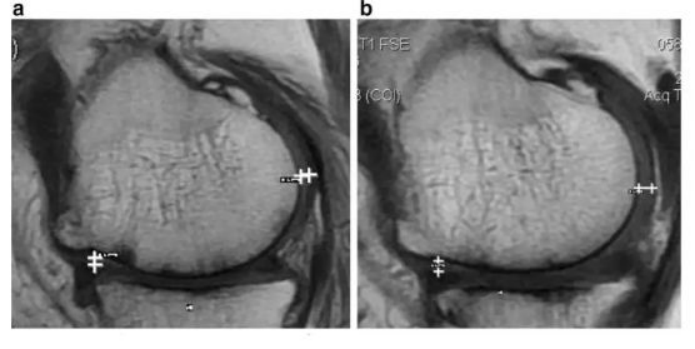

`研究结果:治疗后,,,2年后WOMAC评分也得到改善。。。6分钟内步行距离也显著增加。。。。60%的病人的软骨体积增加。。

如上图所示,,,左图为治疗前,,,右图为治疗后,,白色“+”处示意软骨增厚。。。